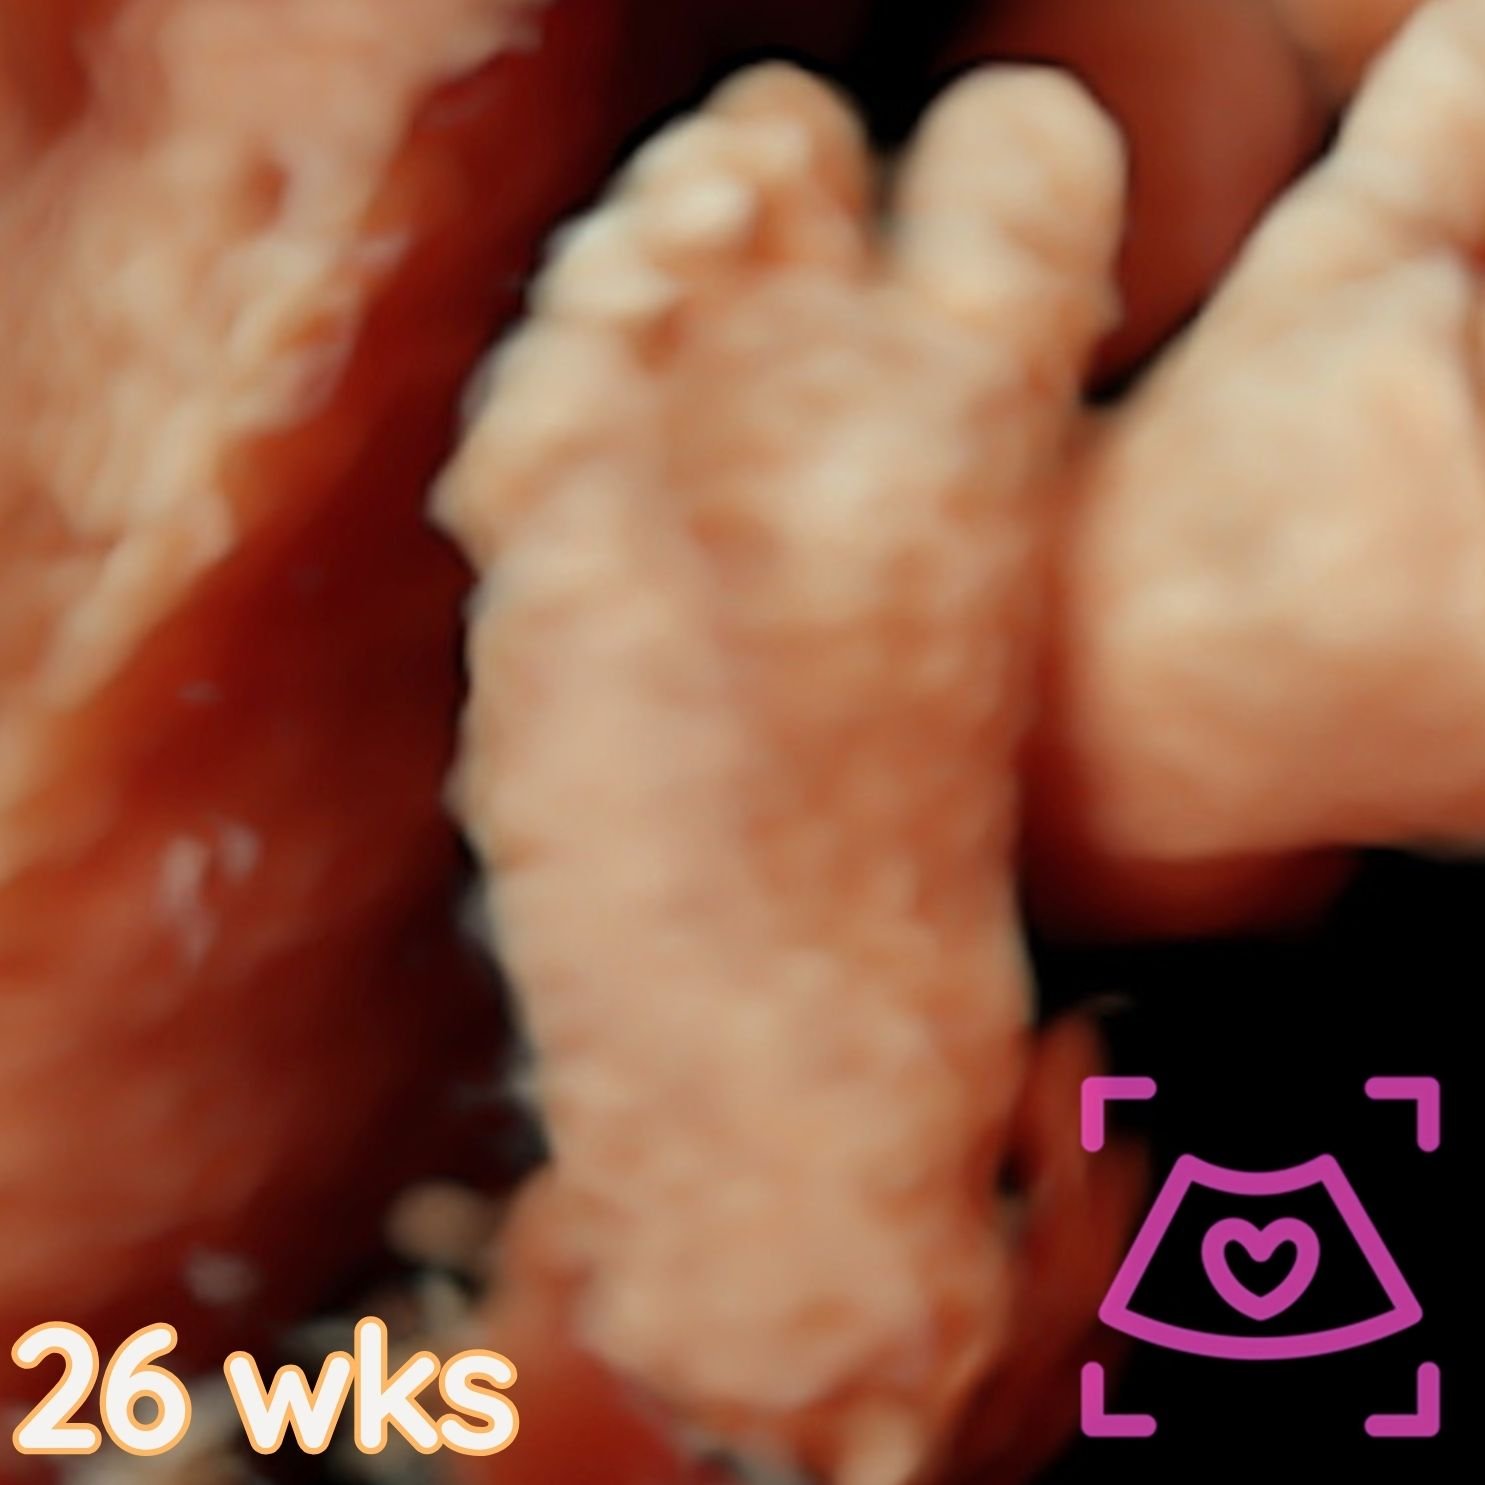

All ultrasounds at this facility are performed abdominally (on top). See examples below from 5-40 weeks! Recommended times can be found on the Services Page and when booking.

2nd Trimester